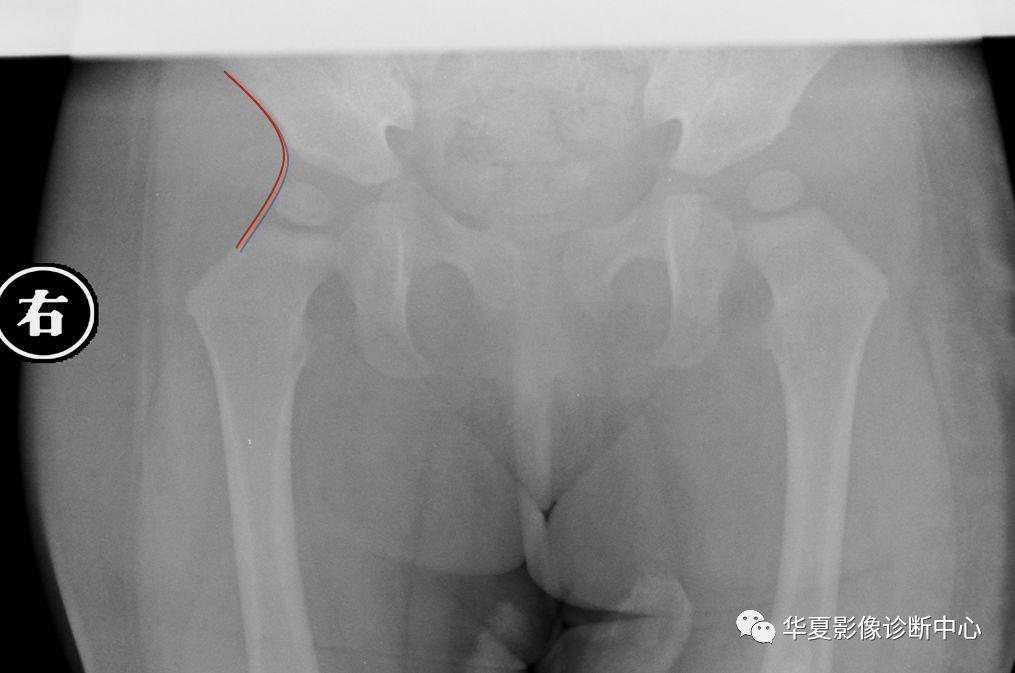

7.外侧线(Calve线)

外侧线(Calve线)即髂翼的外侧面与股骨颈外侧面的弧形连线,正常为连续的。